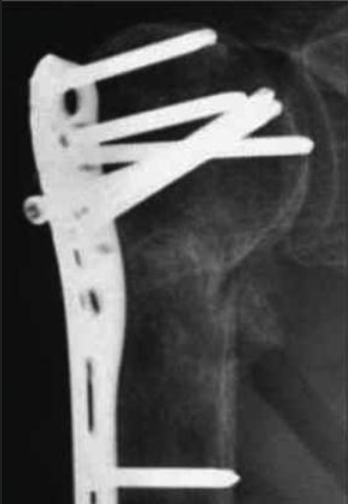

What is the most common complication with this mode of fixation?

Screw cut-out

screw cut-out (up to 14%) is the most common complication following fixation of 3- and 4- part proximal humeral fractures and fractures treated with locking plates